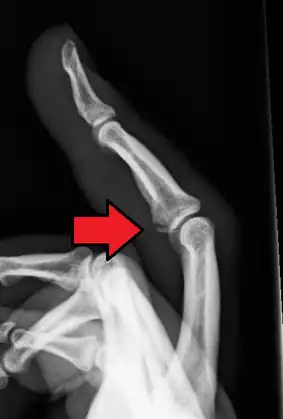

Avulsion fracture of the proximal middle phalanx on the palm side